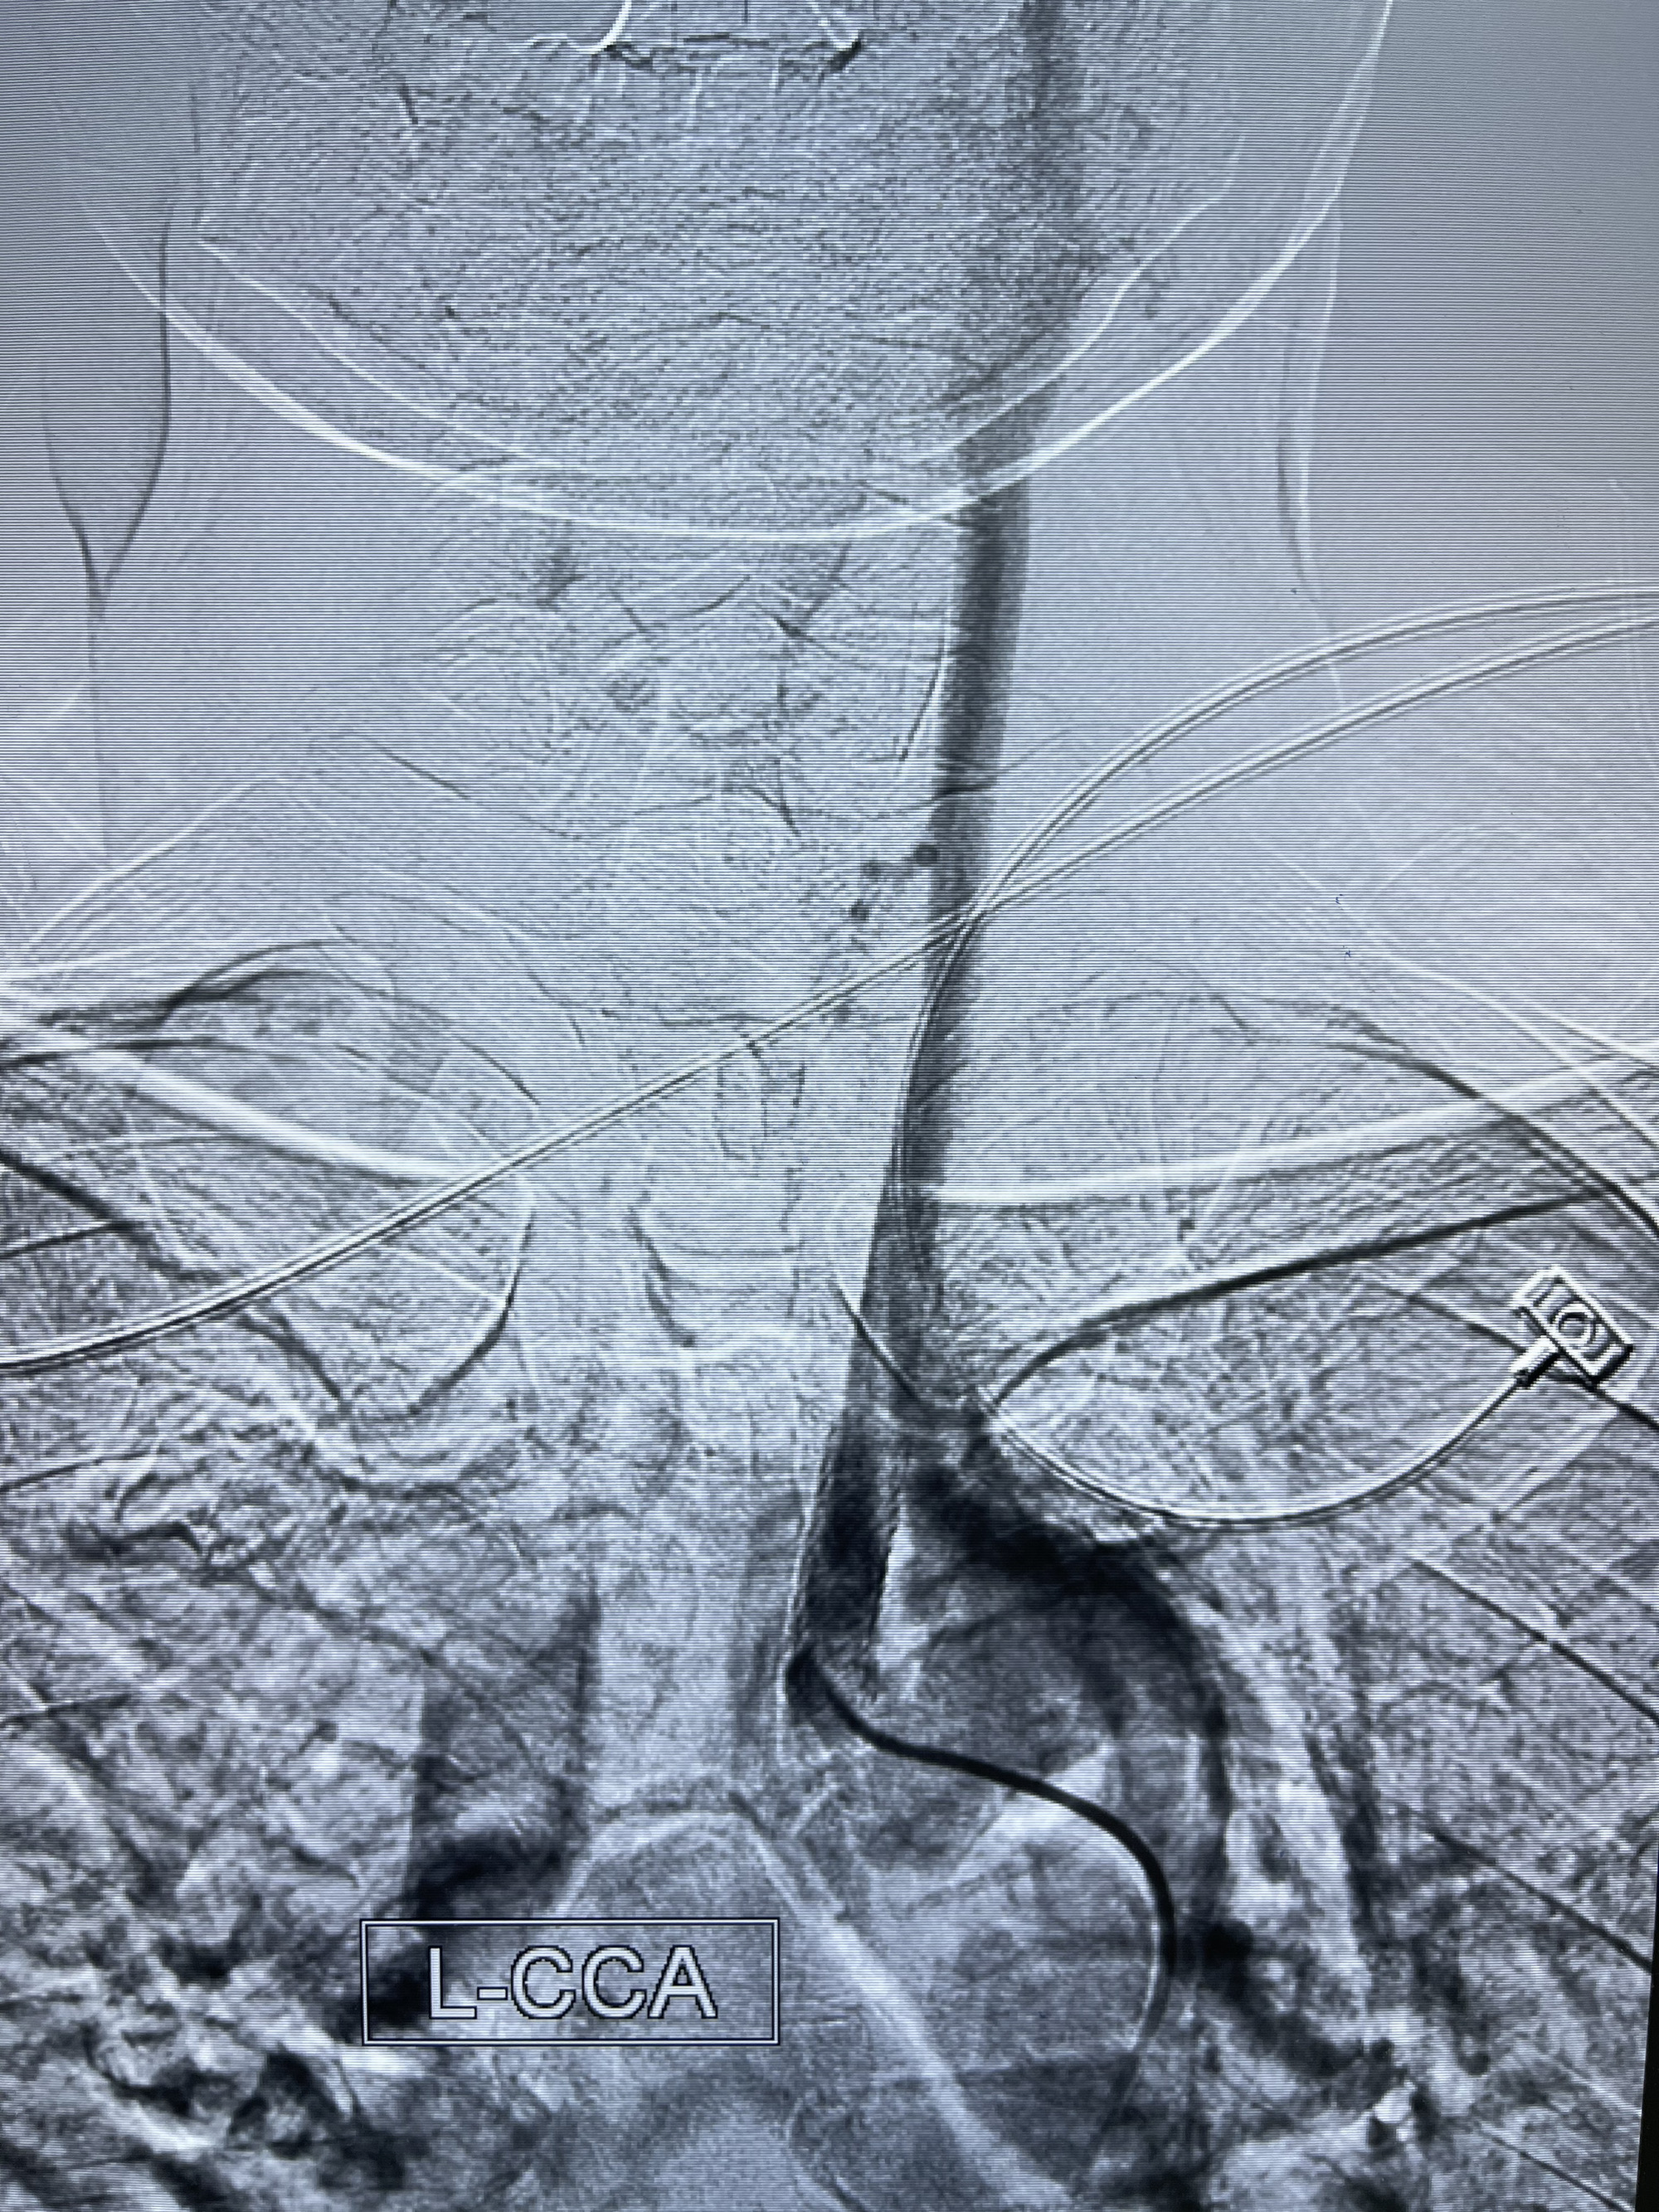

2022-11-21 上海市松江区中心医院 头颅CTA:左侧颈总动脉起始部支架植入状态,管腔通畅,右侧颈内动脉颈段及岩骨段闭塞,右侧颈内动脉破裂孔段动脉瘤。

5.左侧颈总动脉起始部支架术后